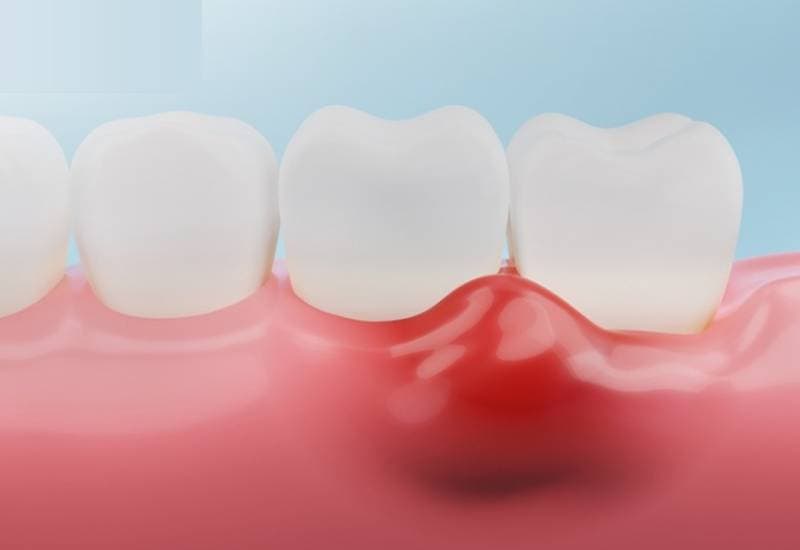

Viêm nướu là tình trạng viêm nhiễm của nướu, gây ra các triệu chứng như sưng đỏ, chảy máu chân răng, hơi thở có mùi hôi, v.v. Đây là bệnh lý rất dễ xảy ra. Đồng thời, khi không được điều trị kịp thời, người bị viêm nướu có thể phải đối diện với những biến chứng nguy hiểm như viêm nha chu, ảnh hưởng đến sức khỏe răng miệng và toàn thân.

– Nướu sưng đỏ

– Tình trạng chảy máu chân răng, thường dễ nhận thấy nhất khi khi đánh răng hoặc dùng chỉ nha khoa

Là một trong những bệnh lý răng miệng phổ biến, nhưng viêm nướu răng thường không được quan tâm đúng cách. Rất nhiều người thường lơ là, phớt lờ bệnh và nghĩ tình trạng này sẽ tự khỏi, chỉ đến khi thấy tình trạng viêm nướu nghiêm trọng hơn mới đi mua thuốc hoặc đi khám. Trong khi đó, các bác sĩ Răng Hàm Mặt của TCI khuyến cáo: Nếu không được điều trị kịp thời, người bệnh viêm nướu có thể gặp biến chứng viêm nha chu, gây tổn thương nghiêm trọng đến mô nướu và xương hàm, thậm chí dẫn đến mất răng.